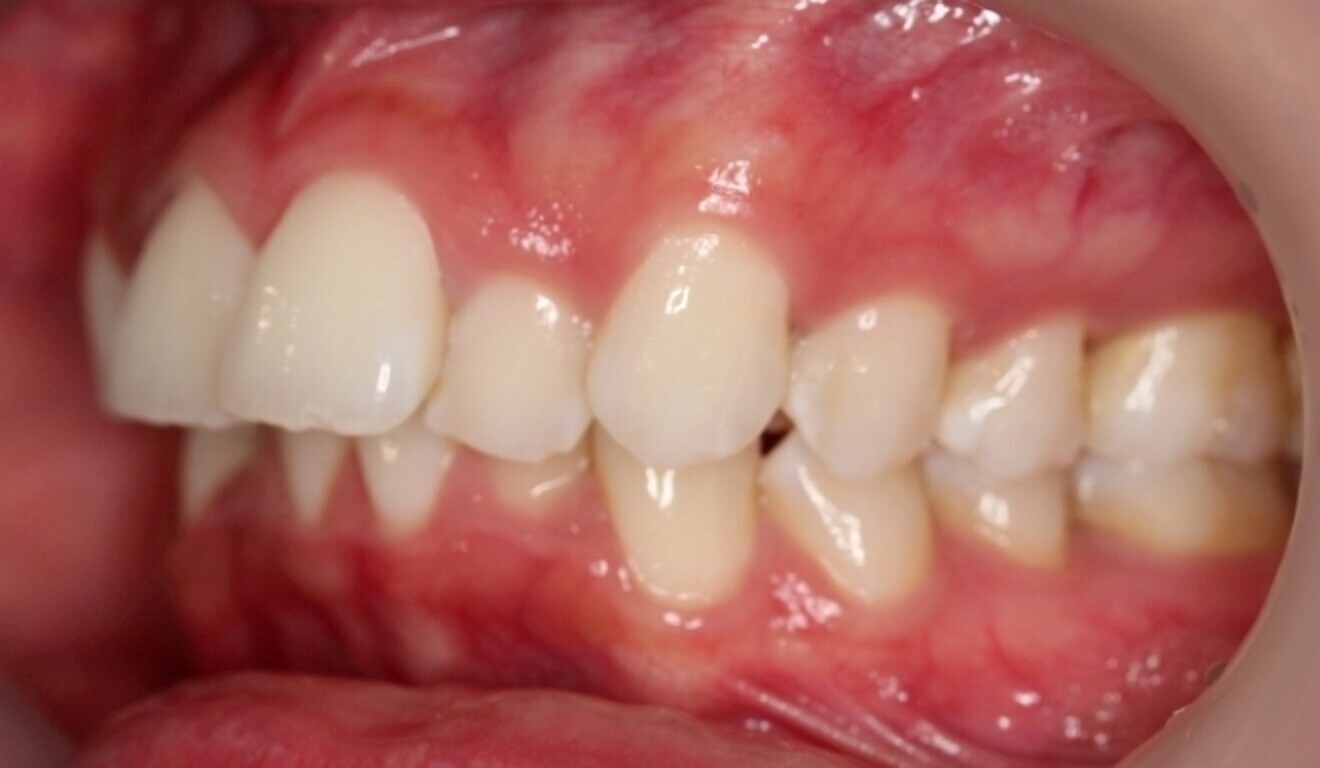

The starting point for Oratomic4D was selecting a real patient to replicate. After an extensive search, the patient, Tina, was chosen for her ideal oral anatomy and range of treatments that could be simulated. Unlike a typodont model, Tina had mild crowding, impacted maxillary and mandibular third molars, and complex root canal anatomy (Figs. 2–7).

These irregularities in Tina’s oral anatomy made her an ideal candidate for the creation of a range of realistic simulation models that are highly representative of the types of patients encountered in dental practice.